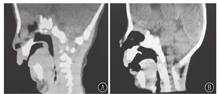

研究期间共收治31例皮罗序列征新生儿。其中男18例,女13例;胎龄34~41周,早产儿2例,足月儿29例;出生体质量1 800~3 700 g。其中并腭裂26例,喂养困难24例,听力异常19例,重度气道梗阻12例(图1),心脏异常12例,放弃治疗出院6例,择期手术出院3例。

22例手术治疗的皮罗序列征新生儿均接受下颌骨牵引成形术,手术年龄为(22.09±8.42) d,手术时体质量为(3 280±430) g。12例重度气道梗阻病例术前行纤维支气管镜检查,2例气管软化,8例喉软化。术后患儿经牵引器牵引长度为10~15 mm,牵引时间为11~15 d,换药时间为14~20 d。术后上机时间为(7.4±2.5) d。术前需有创呼吸机辅助通气11例,无创辅助通气5例,6例仅氧疗或体位疗法。3组重度气道梗阻比例、喂养困难比例比较,差异均有统计学意义(均P<0.05);合并喉软化率、术前体质量增长不良率、术后上机时间和住院时间比较差异均无统计学意义(均P>0.05),但有创呼吸机支持组术后上机时间稍长于其他2组(表1)。22例患儿术后气道梗阻缓解率为100%,下颌后缩的外观完全矫正,均可拔除胃管顺利出院,合并腭裂者使用腭裂专用奶瓶喂养(图2)。于患儿1~4岁时进行电话随访,呼吸困难等呼吸道梗阻表现未复发。

注:A、B、C、D为同一病例在术前、术后第1天(呼吸机支持)、术后第10天(撤机后)、术后第14天(拔除牵引后);E、F为另一患儿术前术后比较 A、B、C and D show the appearance of the same case before surgery,1 day after the surgery (supported by ventilator),10 days after the surgery (ventilator was removed) and 14 days after the surgery (traction was removed),respectively;E and F show appearances of another case before and after surgery